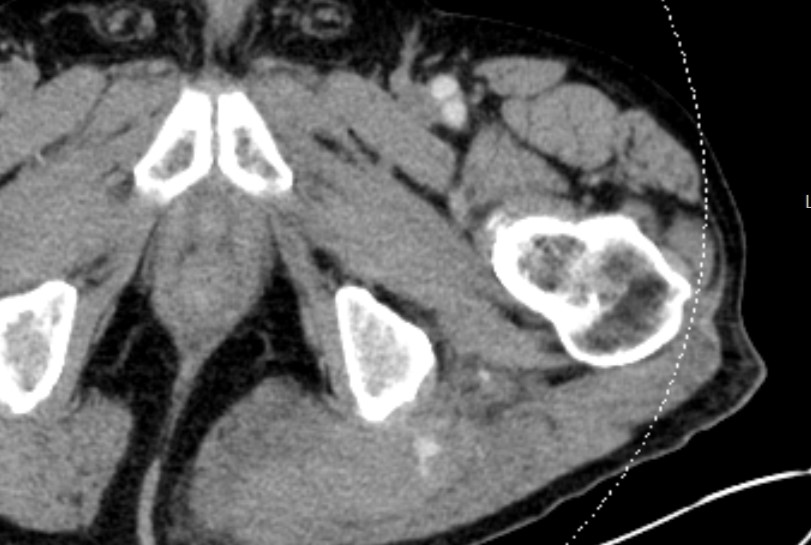

Left gluteal active extrav seen on trauma CT, followed by embolization of an inferior gluteal muscular branch. Follow up CT demonstrates appropriately positioned coils without further extrav. #IRad #TwittIR #VIrad